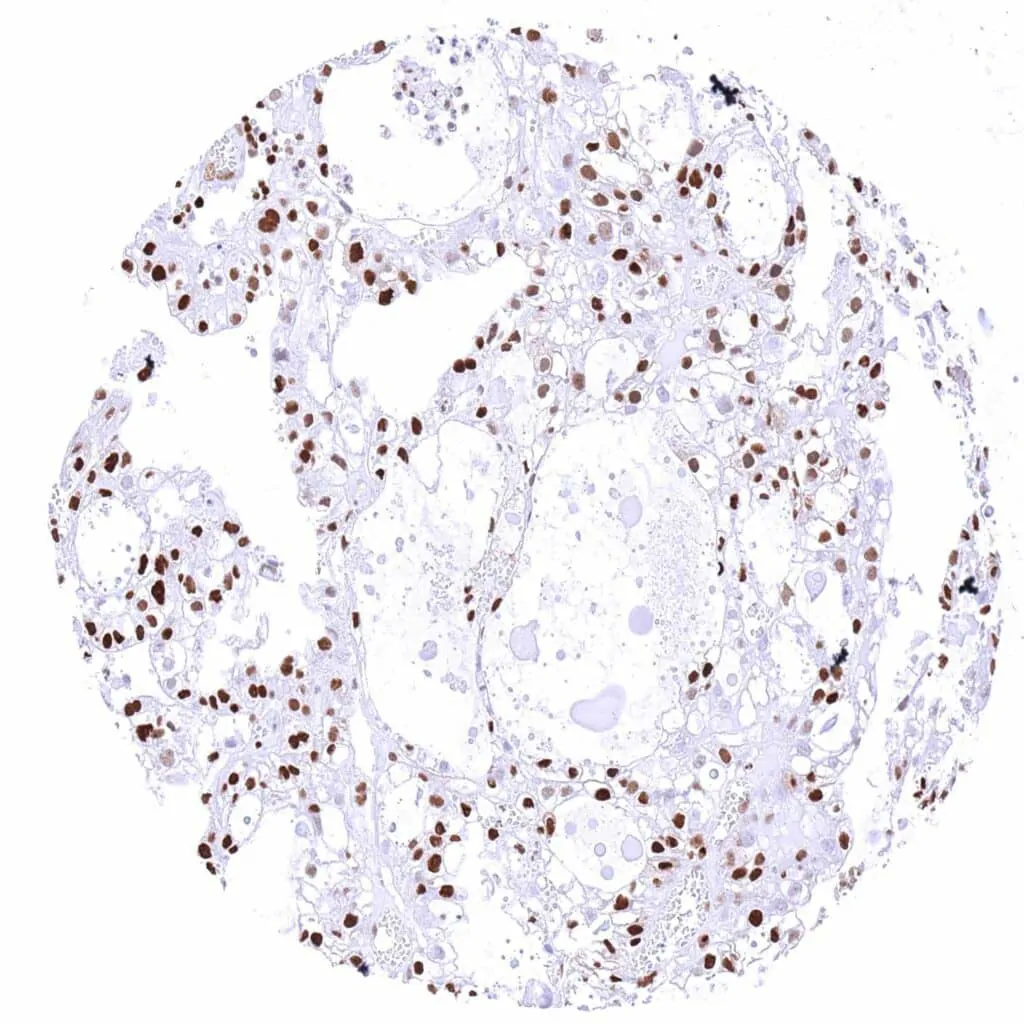

Testis – p27 negative seminoma with strong p27 staining of inflammatory cells and other stroma cells.